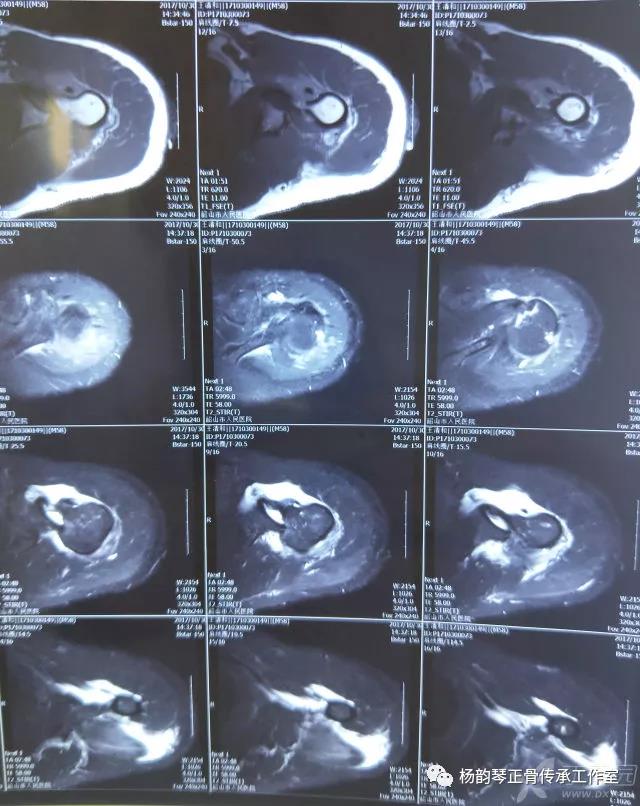

就诊我院后完善CT,诊断明确——左肩关节后脱位:

予以手法复位后拍片复查显示“灯泡征”消失,复位成功。讨论:肩关节后脱位在临床较为少见,特别是影像科经验不足很容易漏报,所以我们临床医生一定要自己仔细阅片,同时要结合体查来进行诊断,防止漏诊。肩关节后脱位时体查也有明显特征:肩关节前方明显变平,喙突较平时明显凸起容易触及,而肩关节后方明显丰满,上臂一般处于内旋内收位,无法主动外旋外展。肩关节后脱位的手法复位相对于前脱位的复位来说也比较容易。患者一般可以取坐位,助手自患侧腋下环抱患者稳定患者躯体,术者一手拉患肢上臂稍牵引内旋,一手自后方推顶肱骨头一般可以复位,如果单纯推顶无法复位也可以术者两手握住伤肢缓慢外展并沿肱骨纵轴牵引,然后逐渐外旋上臂即可复位。整复完成后可以把持患肢作肩关节各个方向的小幅度被动活动,防止肩关节粘连,肩关节后脱位的固定方法与肩关节前脱位的固定方法不同,应将患肢置于上臂外展、后伸、外旋位固定,即外展30度、后伸30度和轻度外旋位,用外展支架固定3周后,循序渐进开始肩关节功能康复。